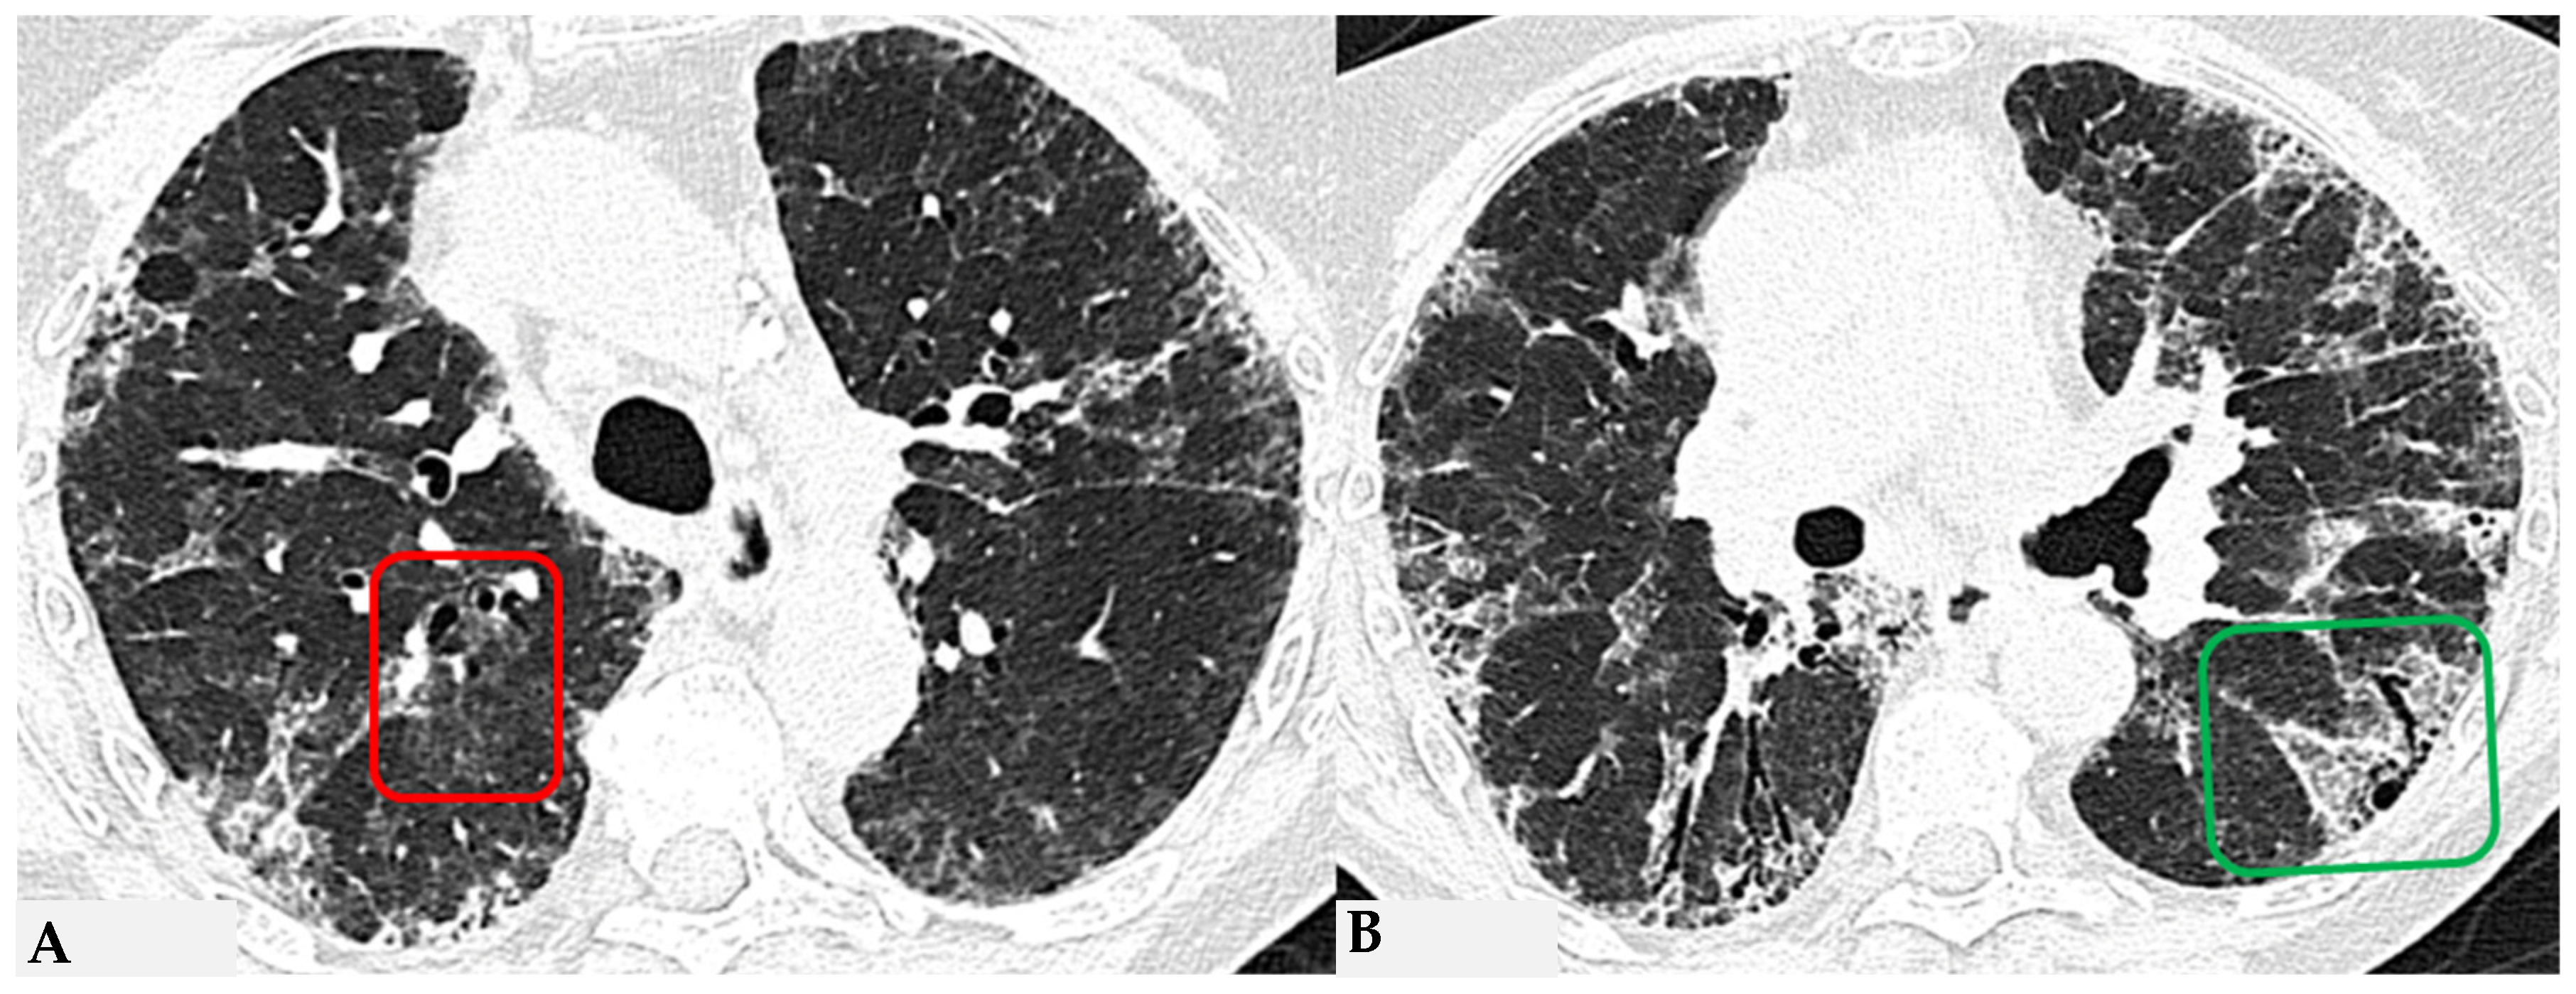

Figure 8.

Axial chest HRCT scan. Asymmetric fibrotic alterations with volume loss on the right in the upper lobe (A); in the lower lobes on the right, a significant extensive area of reduced attenuation is evident, suggestive of air trapping (red box), with components of distorted GGO and fibrosing characteristics with intra- and interlobular thickening and traction bronchiectasis/bronchiolectasis (B).